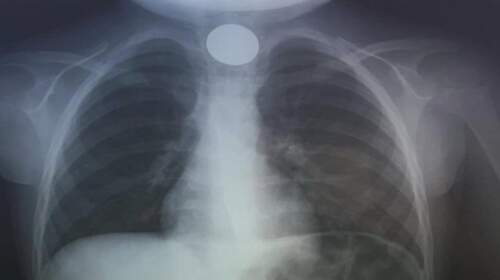

Περιπετειώδες ήταν το τελευταίο βράδυ του 2023 για μία οικογένεια στην Κρήτη, καθώς το 4χρονο παιδί τους, λίγες ώρες πριν την έλευση του 2024, κατάπιε κατά λάθος ένα κέρμα και μεταφέρθηκε εσπευσμένα στο νοσοκομείο του Ηρακλείου. Στιγμές τρόμου έζησαν το βράδυ της παραμονής της Πρωτοχρονιάς τόσο το 4χρονο αγοράκι όσο και η οικογένειά του, στο τέλος όμως όλα πήγαν καλά,…